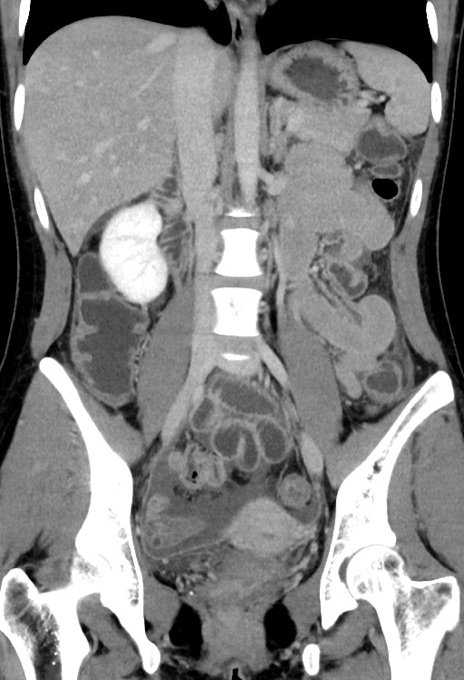

【症例】20歳代女性

【主訴】嘔吐、下腹部痛

【現病歴】昨日夕食後に嘔吐し下腹部痛が出現。本日になっても嘔吐持続し改善しないため来院。

【身体所見】意識清明、BT 37.2℃、BP 108/67mmHg、腹部:平坦、やや硬、下腹部正中から右にかけて圧痛あり、反跳痛軽度あり、tapping pain(+)。

【データ】WBC 13600、CRP 14.94